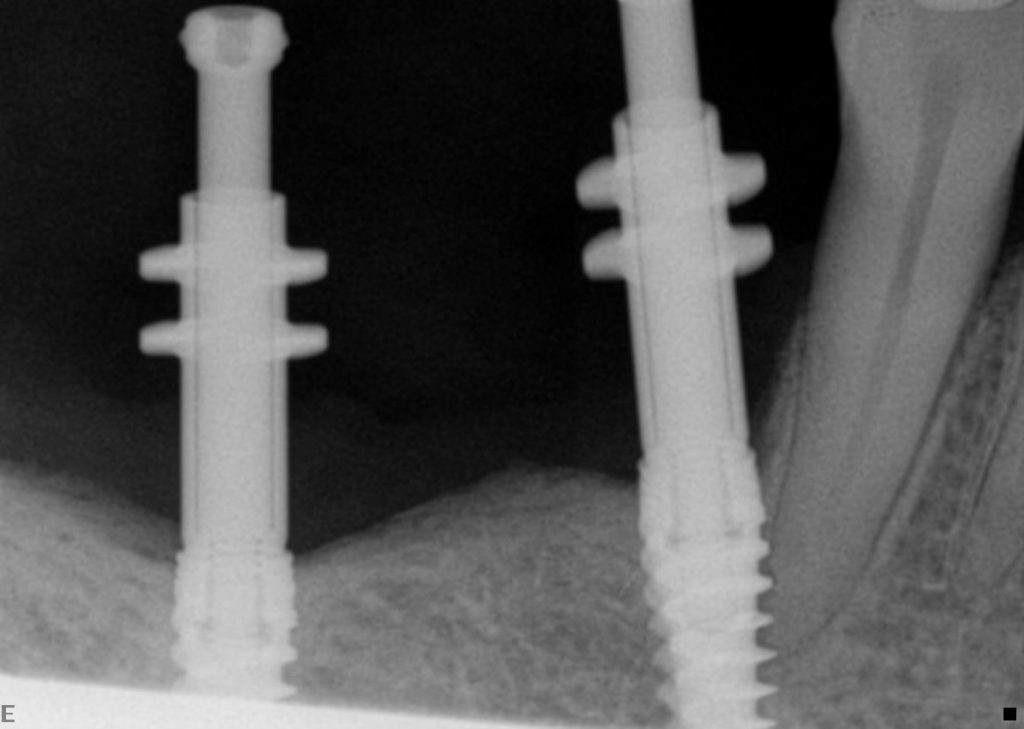

Patient AB attended with 2 unrestored implants placed at another clinic, unfortunately the clinic had closed down. Lower Right 654 were missing.

We were using the same Nobel active implant system and we were able to help. We assessed the patient, his occlusion and his aspirations.

The patient had the implants placed 6 months ago and had lost his temporary acrylic bridge after it had fractured.

One of the implants had been placed very close to the canine tooth, which could jeopardise the nerve of the canine and also the long term integration of the implant.

We used impression posts attached to the implants and took silicone impressions.

2 weeks later a metal porcelain bridge was attached to the implants by way of integral implant screws. patient was very happy to be able to chew on both sides; now he is considering Invisalign.